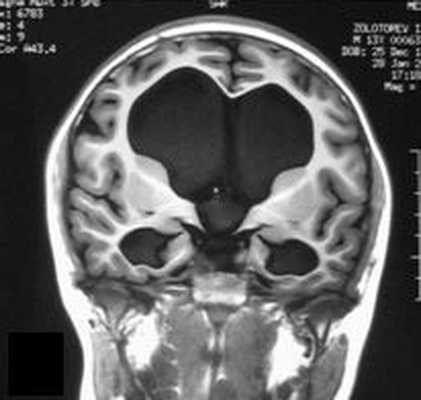

Водянка головного мозга при МР-сканировании в коронарной проекции

Проявления патологии на снимках бывают прямыми и косвенными. Первые связаны с расширением желудочков мозга (III, IV и боковых (в начальном периоде — в области передних рогов и тела)), водопровода и/или субарахноидального пространства (конвекситально, в области базальных цистерн, Сильвиевых борозд и пр.). Косвенные признаки на МР-сканах:

- межжелудочковый индекс свыше 0,5;

- перивентрикулярный отек при напряженной водянке;

- смещение гипоталамуса вниз;

- локальное выпячивание крыши боковых желудочков и др.